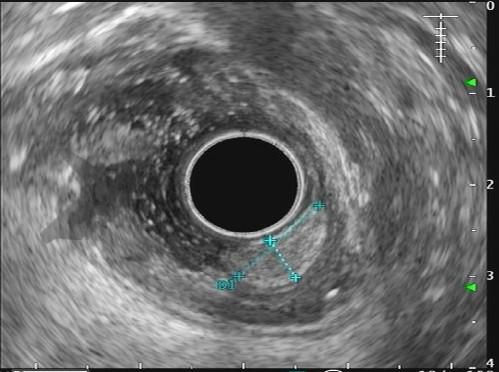

Com relação à ecoendoscopia, o método permite avaliar com muita precisão as camadas e interfaces do trato gastrointestinal, sendo o melhor método de imagem para avaliar e caracterizar as lesões subepiteliais. Com uma frequência de varredura entre 5 a 12 MHz, o ultrassom endoscópico permite distinguir as paredes do TGI em 5 camadas: mucosa superficial (1ª camada ou interface fluído luminal e mucosa), mucosa profunda (2ª camada ou muscular da mucosa), submucosa (3ª camada), muscular própria (4ª camada) e serosa (5ª camada) (figura 4)15,24-26.

Imagem 1. Sinal da almofada (“pillow sign”) Fonte: Kim GH et al.16Imagem 2. Sinal do rolamento (“rolling sign”) Fonte: Kim GH et al.16Imagem 3. Sinal da tenda (“tenting sign”) Fonte: Kim GH et al.16Imagem 4. Ecoendoscopia demonstrando lesão com ecogenicidade hipoecoica, ecotextura homogênea, arredondada, limites bem definidos, contornos regulares, medindo 15 mm x 12 mm e inserida na camada muscular própria. A imagem permite demonstrar as camadas mucosa superficial, mucosa profunda, submucosa, muscular própria. Fonte: arquivos do Instituto do Câncer do Estado de São Paulo (ICESP/HCFMUSP).